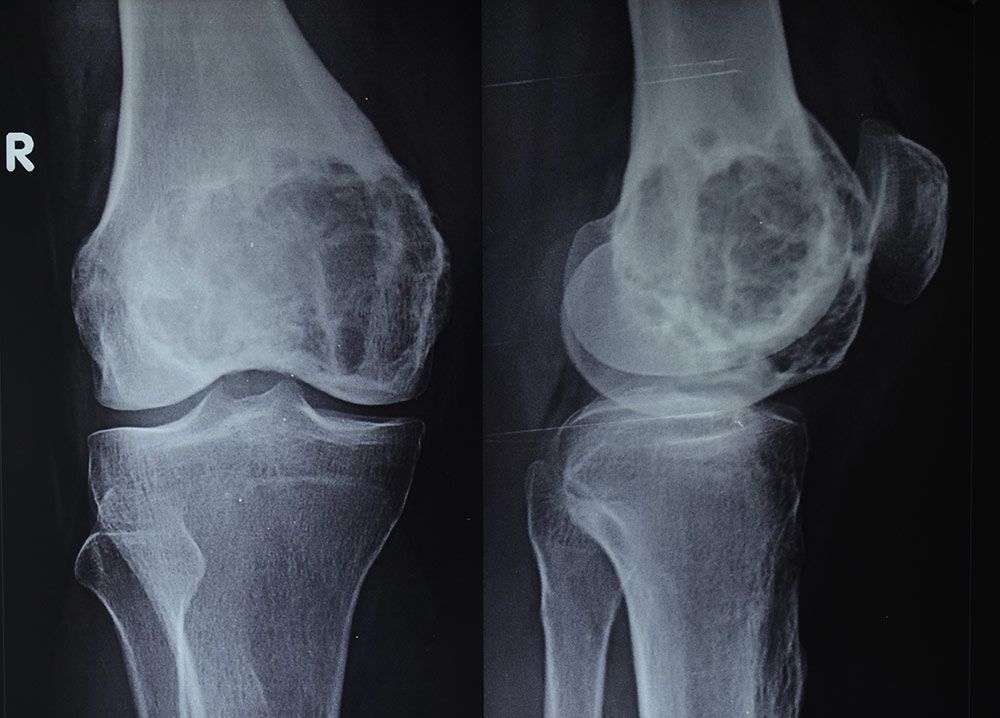

The exact cause of chondroblastoma is not known. The tumors are believed to start from immature cartilage-making cells called chondroblasts